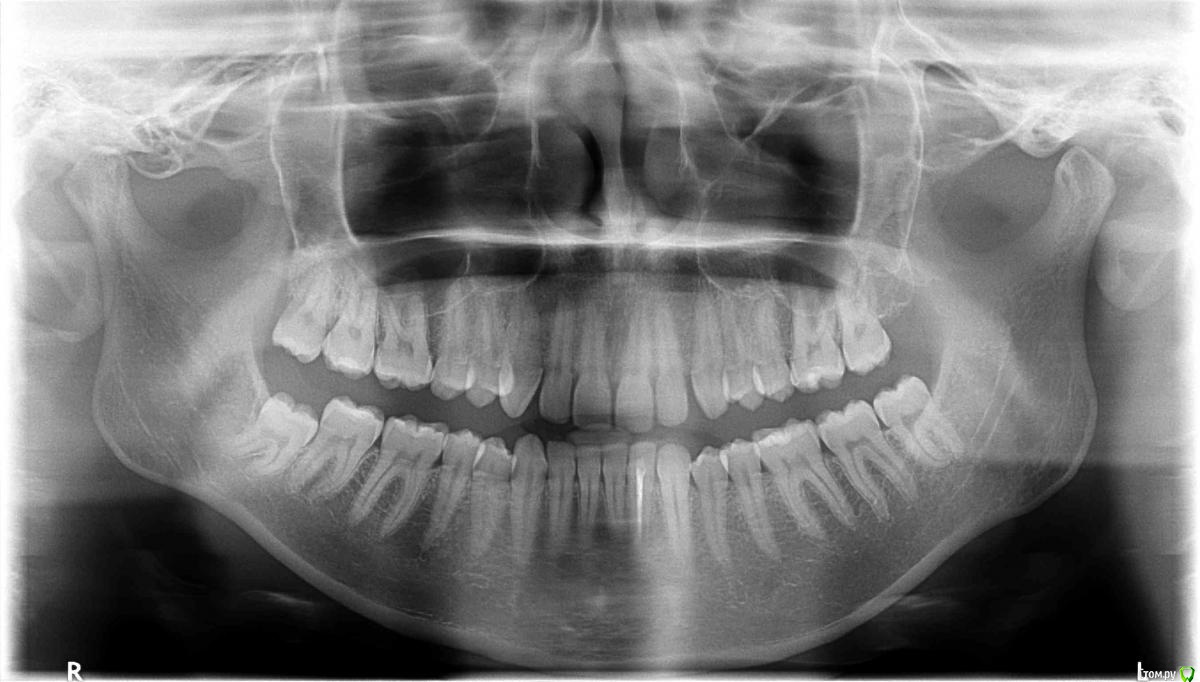

SolnceSamara Опубликовано 24 октября, 2015 Поделиться Опубликовано 24 октября, 2015 почернела старая пломба в давно пролеченной шестерке (сверху). Врач заменила пломбу но зуб болел при надавливании, заменили пломбу повторно-все равно осталась боль, сменила врача-снова сменили пломбу-снова болит, решили депульпировать-снова вынули пломбу, поставили временную-неделю проходила с временной-через неделю окончательно депульпировали, поставили постоянную. Сначало поболело 3 дня, и вроде прошло, хотя остался дискомфорт при надавливании. Прошло 3 недели, боль усилилась, теперь болит не только при надавливании иногда просто звеняще-ноющее ощущение нарастает. Пью нимесил. Посоветуйте что делать-что не так? Снимки прилагаю-делали на протяжении всйх операций (до и после).Разьяснение по снимкам :R1-29/08/15R2,R3-25/09/15R4-R7-28/09/15 Ссылка на комментарий

red_butler Опубликовано 24 октября, 2015 Поделиться Опубликовано 24 октября, 2015 Коллеги поправят, но выглядит как пломбирование одиночным штифтом. Возможно пропущен четвертый канал. Нужна ревизия корневых каналов. 2 Ссылка на комментарий

DmitrySH Опубликовано 24 октября, 2015 Поделиться Опубликовано 24 октября, 2015 Коллеги поправят, но выглядит как пломбирование одиночным штифтом. Возможно пропущен четвертый канал. Нужна ревизия корневых каналов. Все верно. Ссылка на комментарий